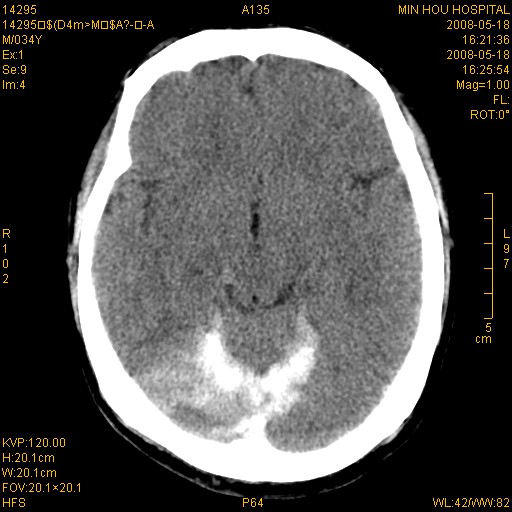

标题: CT13617:双顶叶白质水肿伴大脑镰小脑幕广泛钙化 [打印本页]

标题: CT13617:双顶叶白质水肿伴大脑镰小脑幕广泛钙化

多年前频发抽搐生活不能自理,行ct平扫,诊断为双顶叶占位。因贫未能进一步检查。

目前偶有抽搐,能从事油漆工作。原片未能获取。

双侧侧脑室后脚旁对称性低密度影,符合肾上腺白质营养不良(成人型)改变    小脑幕及大脑廉钙化  可考虑为生理性

支持:1、肾上腺白质营养不良.2、小脑幕、大脑镰广泛钙化。3、建议进一步检查。

硬脑膜钙化是主因,双侧顶叶白质密度减低是可能由于静脉路回流受阻所致。